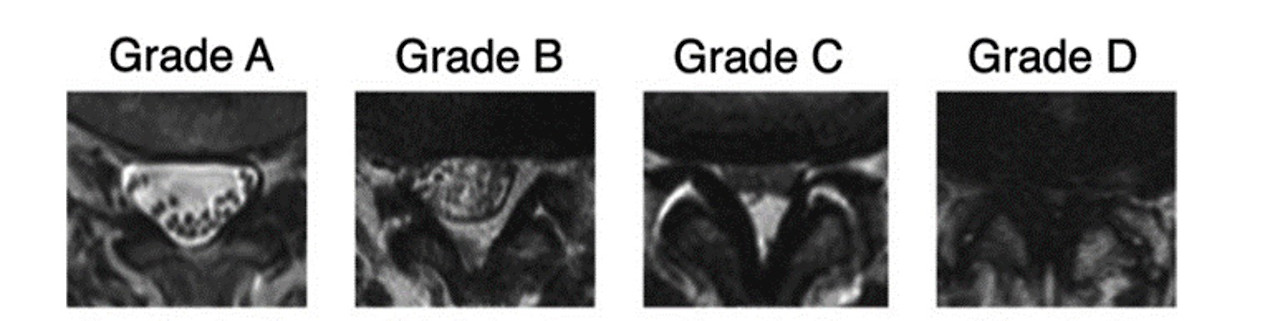

이중 중심성 협착증의 병기가 특히 중요한데, 이유는 노인성 협착증의 많은 부분이 주로 진행된 중심성 협착증이기 때문이다 [Schiaz 2010, Weber 2015].

첫째, 경증 협착증 (1기) – 각각의 신경근이 구분이 되며 뇌척수액 음영이 확실히 보임.

둘째, 중등도 협착증 (2기) – 각각의 신경근이 구분이 되나, 전체 신경낭을 차지하고 있음.

셋째, 중증 협착증 (3기) – 각각의 신경근이 구분이 안되나, 후방의 경막외 지방 음영이 보임.

넷째, 말기 협착증 (4기) – 신경근 구분도 안되고, 지방 음영도 보이지 않음.